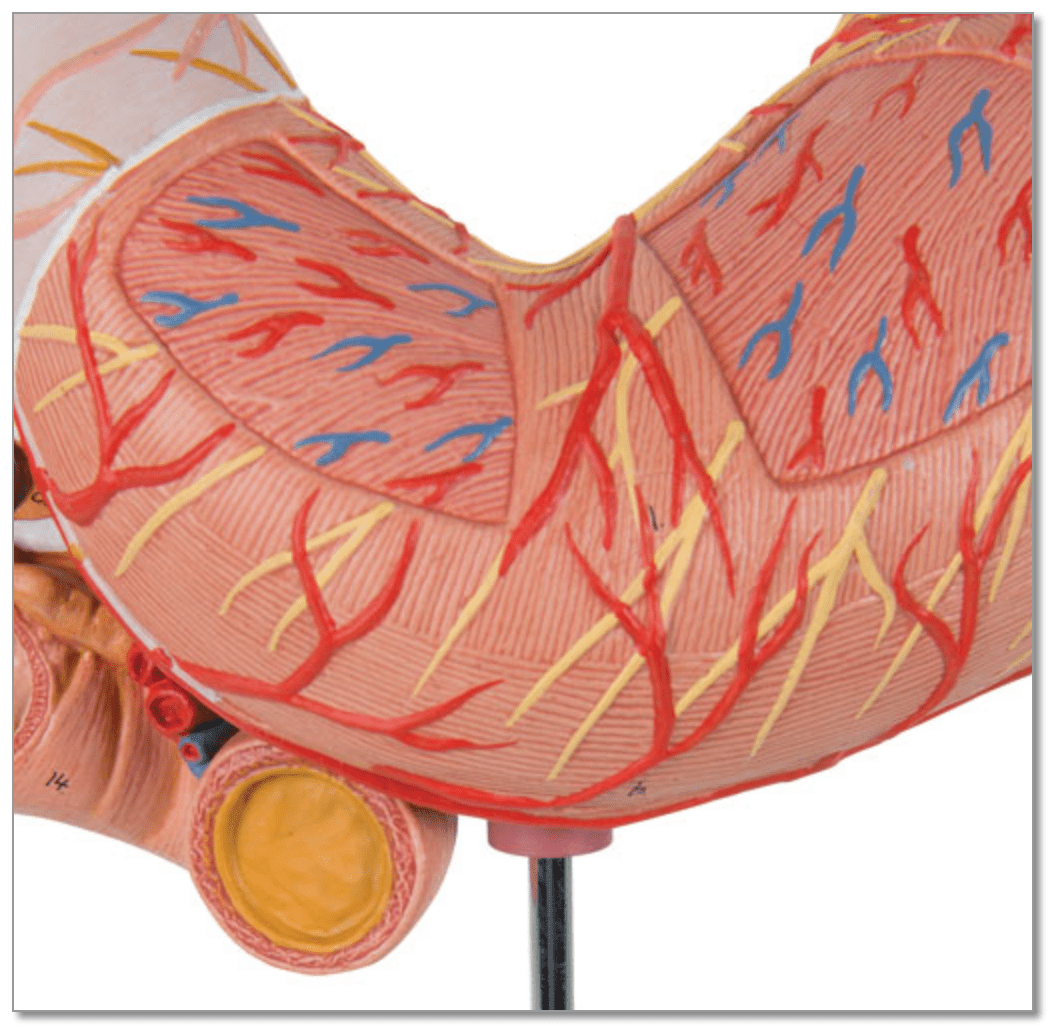

Salg af anatomiske modeller er det bærende element i eAnatomi, selvom vi også bruger mange ressourcer på at udvikle vores egne anatomiske materialer som fx plakater. Anatomiske modeller anvendes til forskellige formål og kan både vise afgrænset væv, organer samt organsystemer. Søger du en simpel model af knoglevæv eller måske en avanceret torso-model baseret på MRI teknologi, kan du finde det hele på eanatomi.com.